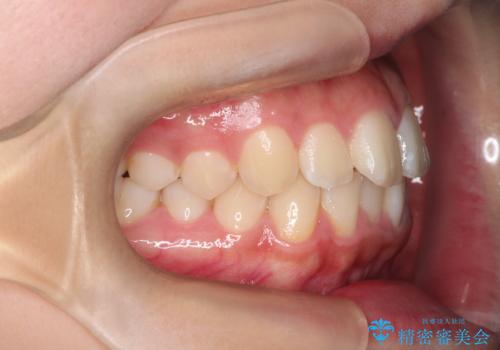

- 患者様は、**下の前歯のがたつき(叢生)**を気にされて来院されました。

できるだけ目立たずに治療を進めたいというご希望があったため、インビザラインによるマウスピース矯正をご提案しました。

診査の結果、インビザラインでの対応が可能と判断し、全体の咬合バランスにも配慮した上で、治療計画を立てました。